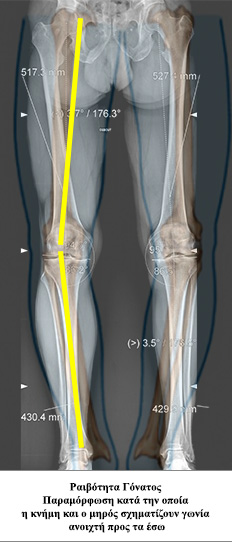

• - Ονομάζεται η απόκλιση του άξονα του γόνατος κατά την οποία η κνήμη και ο μηρός σχηματίζουν γωνία ανοιχτή προς τα έσω. Κατά την παραμόρφωση αυτή τα φορτία του σώματος διέρχονται κυρίως από την έσω πλευρά του γόνατος (έσω μεσάρθριο διάστημα), με αποτέλεσμα αυτό να φθείρεται πιο εύκολα και γρήγορα.

• - Αποτελεί πρώιμο ακτινολογικό δείκτη της αρθρίτιδας του γόνατος.

• - Απλός ακτινολογικός έλεγχος που να περιλαμβάνει και τα δύο κάτω άκρα με σκοπό την ακριβή μέτρηση της παραμόρφωσης.